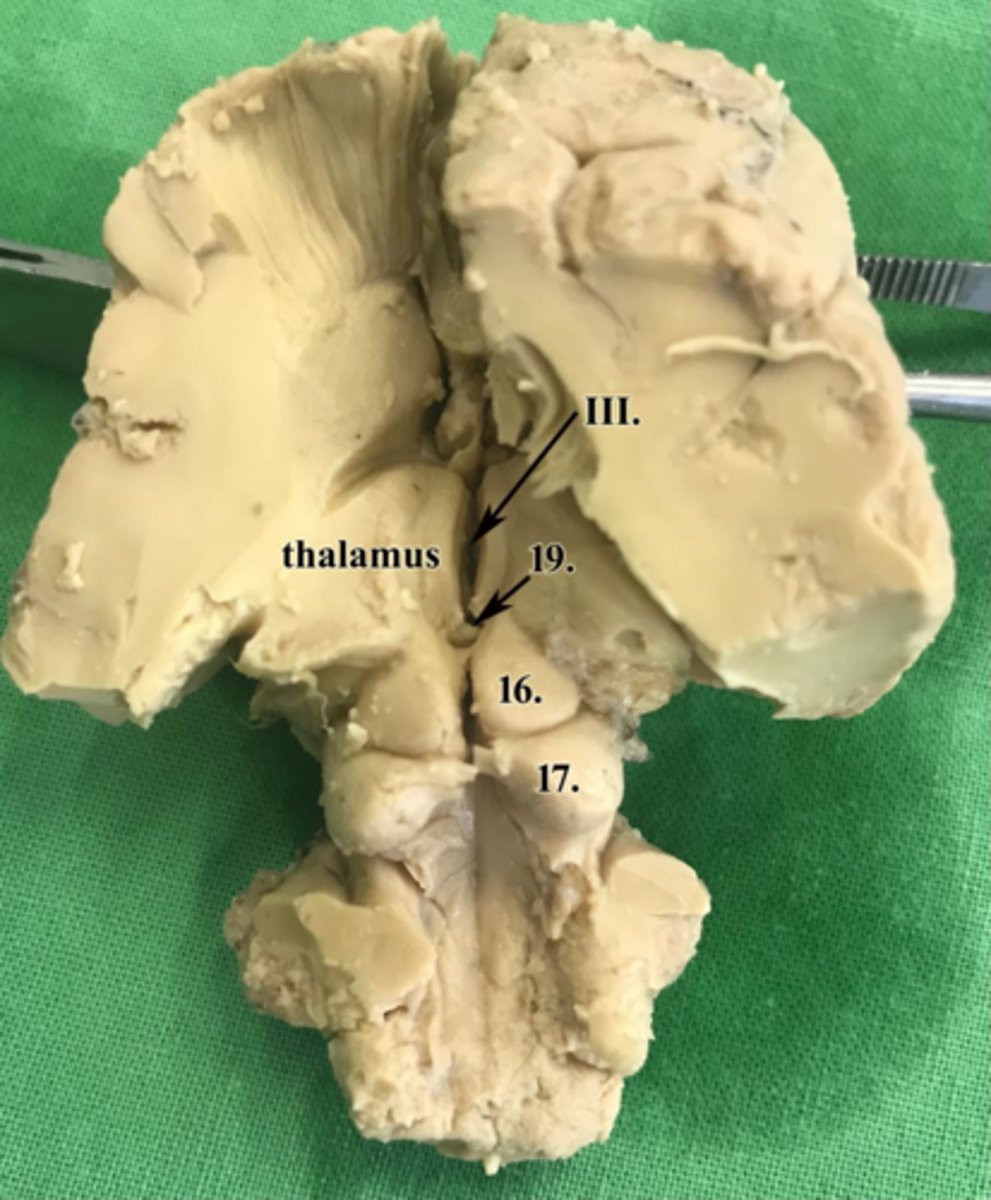

colliculi rostrales

16

colliculi caudales

17

glandula pinealis

19

ventriculus tertius

III

adhesio interthalamica

18